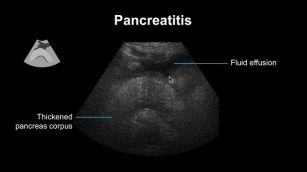

Diagnosing pancreatitis with the help of ultrasound. 14th Nov 2017 - Nikolaus Mayr, MD [VIDEO 6:15] Learn how to diagnose pancreatitis using ultrasound in this short video.